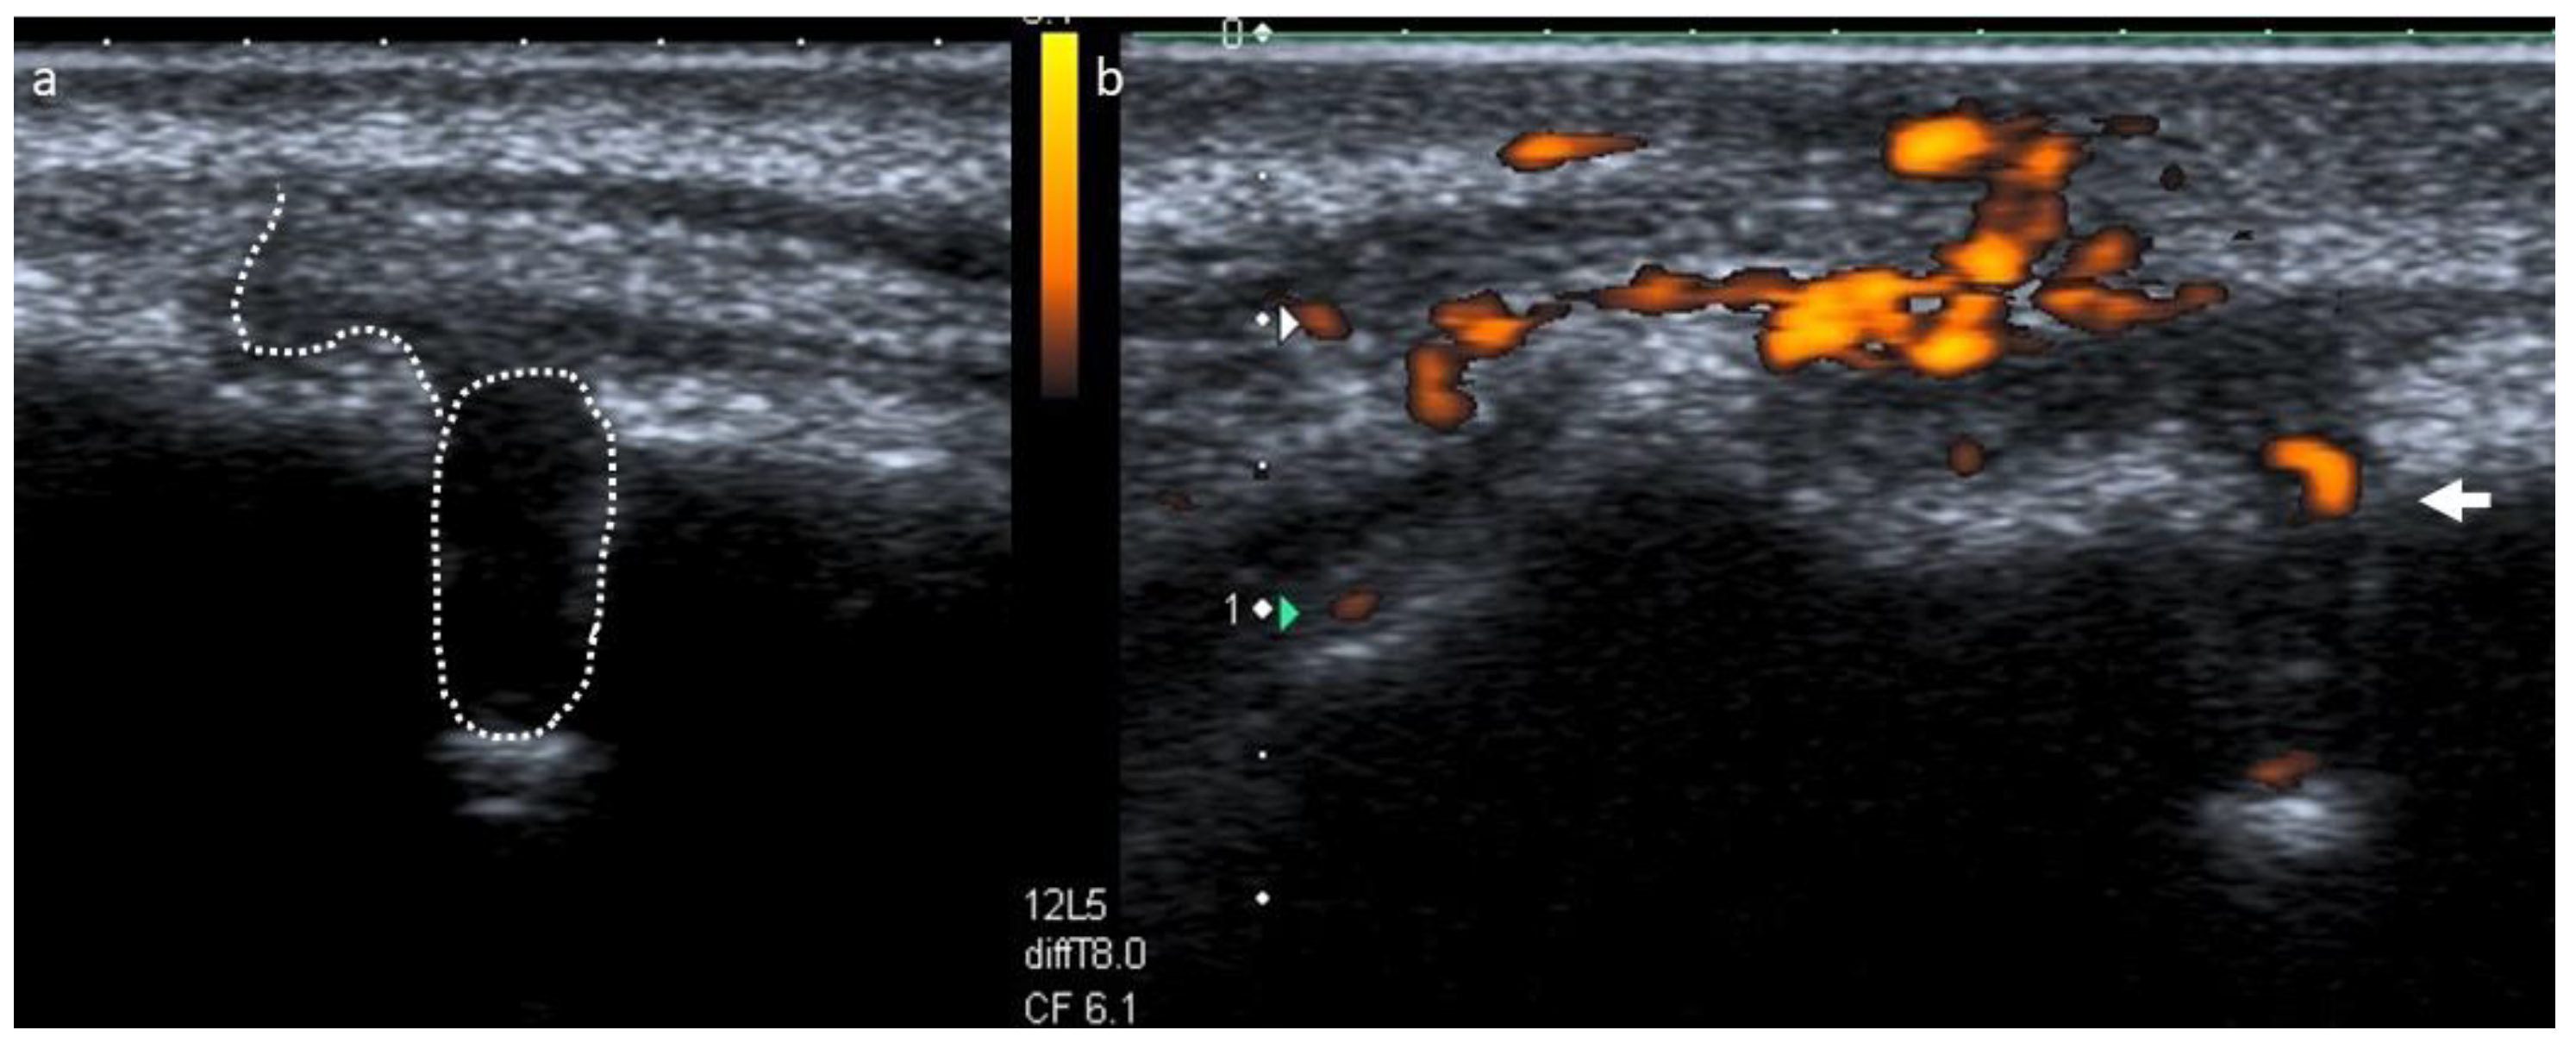

- Cotti, E.; Esposito, S.A.; Musu, D.; Campisi, G.; Shemesh, H. Ultrasound examination with color power Doppler to assess the early response of apical periodontitis to the endodontic treatment. Clin. Oral Investig. 2018, 22, 131–140. [Google Scholar] [CrossRef]

- Cotti, E.; Musu, D.; Goddi, A.; Dettori, C.; Campisi, G.; Shemesh, H. Ultrasound examination to visualize and trace sinus tracts of endodontic origin. J. Endod. 2019, 45, 1184–1191. [Google Scholar] [CrossRef]